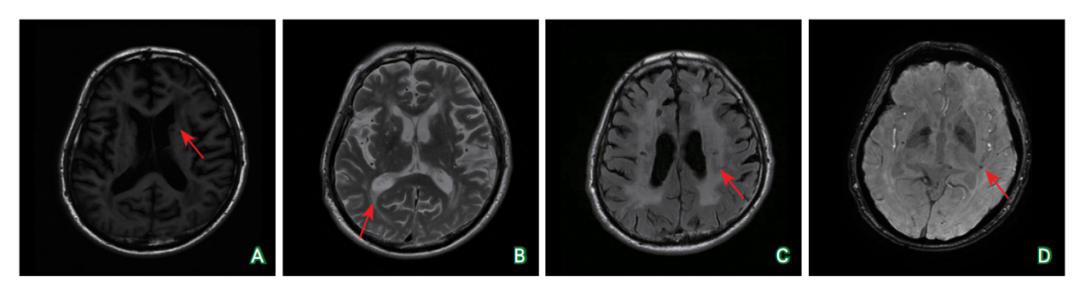

医脉通-临床病例平台 患者男性,67岁。主因“头晕1天,视物不清20小时”于2022年4月25日入院。患者入院前1天无明显诱因出现头晕,伴左侧视物不清、恶心,无 既往史: 入院查体:左上臂血压126/71 mmHg(1mmHg=0.133kPa)、右上臂血压132/70 mmHg,心率54次/分,律齐。神清语利;定向力、记忆力正常,计算力、判断力减退;颈软,Kernig征阴性;双侧瞳孔等大等圆,对光反射灵敏,眼球各方向活动正常,眼震未见异常,左侧视野同向偏盲;双侧额纹、鼻唇沟对称,伸舌居中;四肢肌张力正常,肌力Ⅴ级,共济稳准;感觉系统未见异常;四肢肌腱反射对称(++),双侧Babinski征(+),双侧掌颌反射(+)。NIHSS评分2分。 实验室检查(2022-04-26):空腹血糖7.3 mmol/L↑、 影像学检查:头颈部CTA(2022-04-26)示双侧颈总动脉、颈内动脉、颈外动脉、锁骨下动脉及无名动脉显示清晰,未见有意义狭窄或局限性扩张;双侧椎动脉均衡供血,走行自然,显示清晰,未见狭窄及局限性扩张;双侧大脑前动脉、大脑中动脉、大脑后动脉及基底动脉走行分布正常,未见明显狭窄;大脑前交通动脉可见显示,后交通动脉未见开放(图1B)。回顾既往影像检查,头颅MRI和SWI(2022-04-03)示双侧额叶皮质下、顶叶皮质下、颞叶皮质下、枕叶皮质下、半卵圆中心、侧脑室旁白质以及基底节区见多发点片状等/稍长T1信号、稍长T2信号,FLAIR为高信号;双侧额叶、顶叶、颞叶、基底节区、丘脑可见SWI低信号(图4)。MMSE评分25分,MoCA评分16分。 诊疗经过:入院后给予20 %甘露醇125 mL静脉输注,1次/8小时;0.9 %氯化钠溶液500 mL+15%氯化钾10 mL静脉输注,1次/日;继续服用二甲双胍,500毫克/次,3次/日;停用阿司匹林和阿托伐他汀。5月16日查体:左侧视野同向偏盲,双侧Babinski征(+),双侧掌颌反射(+)。NIHSS评分2分。复查头颅CT(2022-05-16)示右侧枕叶团片状稍高密度影,较4月25日头颅CT密度明显减低,周围环绕脑组织低密度改变(图1C)。遂出院,门诊随诊。 A:头颅CT(2022-04-25)示右侧枕叶多发团片状高密度影,周围环绕脑组织水肿(箭头所示);B:头颈部CTA(2022-04-26)示颅内外动脉未见明显狭窄及局限性扩张;C:头颅CT(2022-05-16)示右侧枕叶团片状稍高密度影,周围环绕脑组织低密度改变,较4月25日明显好转(箭头所示)。 图1 头颅CT平扫及头颈部CTA扫描结果 黑色箭头所示为先证者(患者);患者父亲、1个同父异母的哥哥有偏头痛病史并均已去世。 图2 患者的偏头痛家系 基因检测提示c.1774C>T杂合突变(红色圆圈所示) 图3 NOTCH3基因检测 A:T1WI序列双侧皮质下、侧脑室旁白质及基底节区可见多发点片状稍长T1信号(箭头所示);B:T2WI序列上述部位可见多发点片状稍长T2信号(箭头所示);C:FLAIR序列脑室旁、皮质下白质可见点片状高信号(箭头所示);D:SWI序列双侧额叶、顶叶、颞叶、基底节区、丘脑可见低信号(箭头所示)。 图4 头颅MRI平扫结果(2022-04-03) 患者最终诊断是什么?其常见临床表现有哪些?其并发脑出血的危险因素都有哪些? (查看原文参与互动讨论)